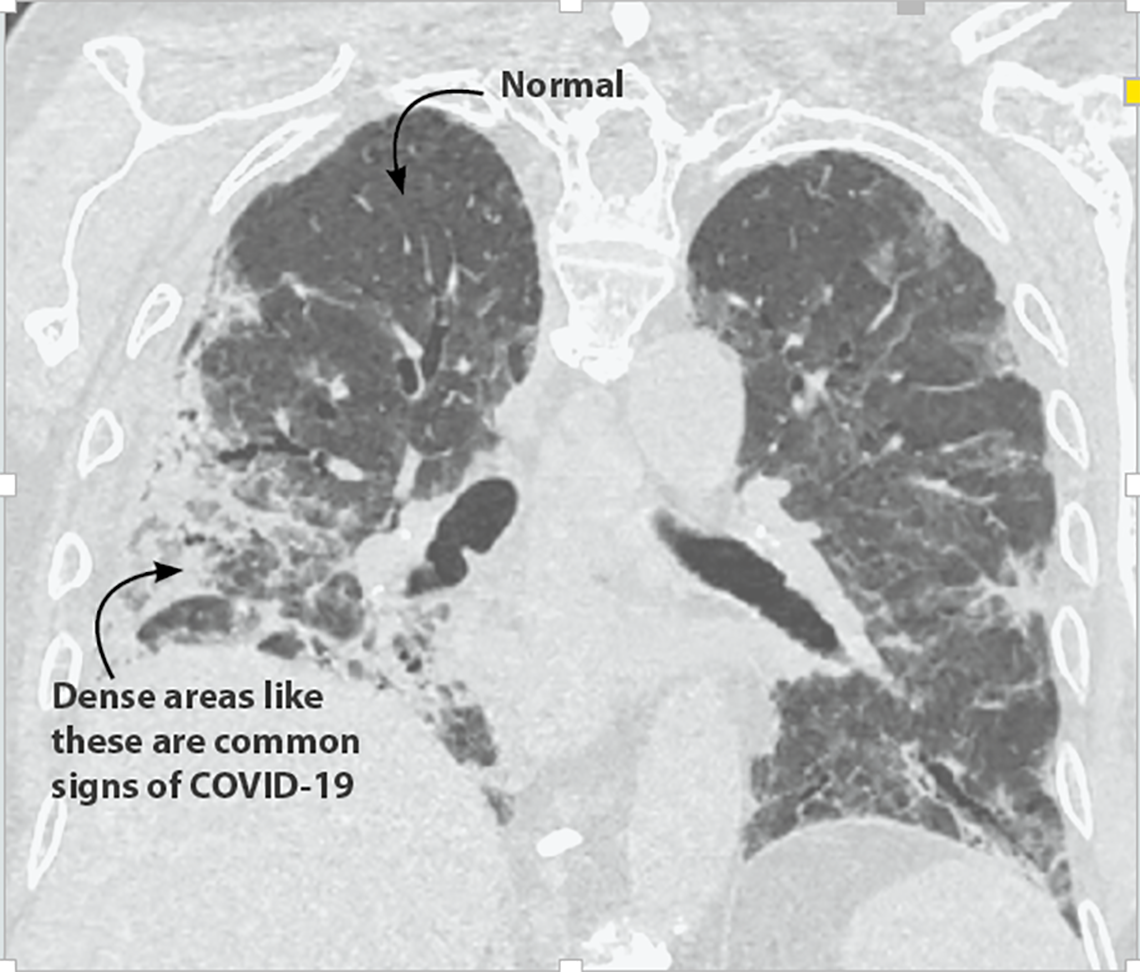

Getting images of what’s happening inside of people’s bodies is helping health professionals to evaluate and better understand the COVID-19 disease, which is caused by a newly discovered coronavirus.

“Diagnostic imaging is a window into the body,” said Olivier Pellet, a radiologist at the IAEA. “It has allowed us to uncover complications, such as lesions, pneumonia or blood clots in the lungs. Every day we learn about the virus and its impact on the human body, while discovering new COVID-19-related signs and symptoms we have not seen before, even when a person may otherwise appear asymptomatic.”

While there are a range of imaging techniques available, the three most widely used methods for evaluating COVID-19 patients are chest X-rays, chest computed tomography (CT) and lung ultrasound.

“These three techniques are complementary and offer options for evaluating how COVID-19 affects different organs at different stages,” said Pellet. “The reason they are used on the lung and chest area is because respiratory symptoms have been known to be among the first signs of COVID-19.”

Although diagnosing COVID-19 relies on identifying the virus using laboratory tests such as reverse transcription–polymerase chain reaction, medical imaging is widely used to evaluate patients at various stages of the disease, particularly for those with moderate, severe or critical cases.

A computed tomography (CT) scan is a set of multiple X-ray images. A CT machine rotates around the patient and rapidly sends X-rays through the body from multiple angles. A ring of hundreds of specialized detectors around the body track the pattern of the X-rays. This is then processed by the machine’s powerful computer to create detailed images constructed out of very thin slices of the body, up to 0.3 mm wide, often in 3D. For a CT scan of the chest, which is the area of the body typically scanned when evaluating COVID-19, hundreds of images are generated to cover the whole chest area.

CT machines are more sophisticated, more expensive and not as widely available as X-ray machines. They are also harder to decontaminate, which can take more than 20 minutes, said Pellet. “CT scans provide highly detailed information and to do that they use more radiation than an X-ray machine. They should therefore only be used when appropriate for the patient’s case.”